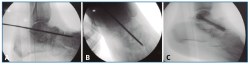

Figura 2. Cruentación de la articulación subastragalina, bajo control fluoroscópico, hasta tejido subcondral, con escoplos (A) y brocas motorizadas (B y C).

En segundo lugar, se aborda la articulación ST como indican Carranza et al.(30), se penetra la ST anterior y media por una incisión solo cutánea de 1 cm sobre el seno del tarso y la ST posterior por un portal posterolateral justo lateral al tendón de Aquiles, similar al portal artroscópico posterolateral descrito por van Dijk(31). Por estos 2 portales, finalmente se cruenta la articulación bajo control fluoroscópico hasta tejido subcondral con escoplos y brocas motorizadas (Figura 2).